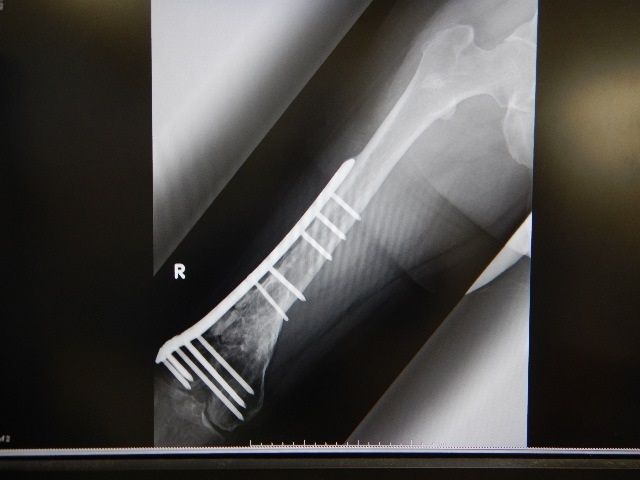

±¦ÂÄê´ü¸¡ºº

ºòÆü¤ÏÎ×»þµÙ¶È¤ò夤¤Æ¡¢È¾Ç¯Ëè¤Î±¦Â¤ÎÄê´ü¸¡ºº¤Ë¹Ô¤Ã¤Æ¤¤Þ¤·¤¿¡£

»ö¸Î¤«¤é10ǯ°Ê¾å·Ð²á¤·¤Æ

2ǯ´Ö¹ü¤¬·Ò¤¬¤é¤ºµ¶´ØÀ᤬¤¢¤ê

Áϳ°¸ÇÄê¤Ç¸ÇÄꤷ¤Æ¤¤¤¿¤Î¤ò

¥í¥Ã¥¥ó¥°¥×¥ì¡¼¥È¤ËÊѹ¹¤·¤Æ8ǯ

Åö»þ¤Þ¤À»î¸³Ãʳ¬¤À¤Ã¤¿Ä¶²»ÇȹüÀÞ¼£ÎÅË¡¤Ç¤ä¤Ã¤È¹ü¤¬·Ò¤¬¤¿¡£

¤½¤Î¼£ÎÅ¤Î¿ØÆ¬»Ø´ø¤ò¼è¤Ã¤ÆÄº¤¤¤¿ÃæÀ¥Dr¤¬¤ªË´¤¯¤Ê¤ê¤Ë¤Ê¤Ã¤¿¡¦¡¦¡¦

Áϳ°¸ÇÄê¼£ÎÅË¡¤Î¸¢°Ò¤Ç´ØÀ¾â1¤ÎDr¤Ç¤·¤¿¡£

Åö»þËͤΤ郎¤Þ¤Þ¤òʹ¤Æþ¤ì¤ÆÄº¤¡¢¤È¤Æ¤â¤ªÀ¤Ïäˤʤä¿Êý¤Ç¤¹¡£

¤´Ì½Ê¡¤ò¤ªµ§¤êÃפ·¤Þ¤¹¡£